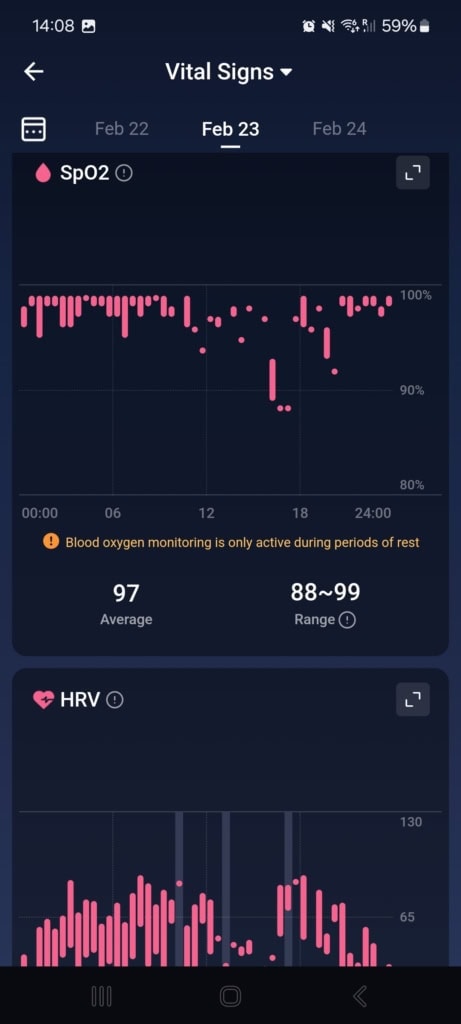

Stan funkcji życiowych (Znaki życia)

W tej części aplikacji dowiesz się o całodziennych wahaniach tętna i jego zmienności, nasyceniu krwi tlenem, częstotliwości oddechów podczas snu i temperaturze snu. Aplikacja porównuje wszystkie te dane z twoją własną referencją z ostatnich 7 do 30 dni oraz z referencyjnymi wartościami medycznymi. Gdy tylko w ciągu dnia lub nocy osiągniesz wartości, które nie mieszczą się w referencyjnych granicach, aplikacja cię o tym poinformuje.

Najczęściej spotykałem się z wyraźnym spadkiem zmienności tętna i wzrostem samego tętna. Te wahania pojawiały się czasem podczas snu, aktywności sportowej lub w przypadkowych sytuacjach, o których nie miałem pojęcia. Mimo że doceniam ten kompleksowy wgląd w moje funkcje życiowe, brakowało mi podczas testowania kontekstu. Funkcja oferuje jedynie wartości i spostrzeżenia, że coś jest nie tak. Nie znalazłem w aplikacji żadnych wskazówek dotyczących możliwych przyczyn ani rekomendacji działań, które mogłyby pomóc przywrócić stan do normy.

Mimo że nietypowe wartości nie mają jasnego kontekstu, aplikacja zwraca na nie uwagę i pyta, co mogło być ich przyczyną (spożycie alkoholu, infekcja, kofeina i inne). W moim przypadku działało to idealnie. Popełniłem błąd dietetyczny, przez który dostałem gorączki i problemów trawiennych. Mój ogólny stan znacznie się pogorszył, co objawiło się wyraźnym spadkiem jakości snu, obniżoną zmiennością tętna i podwyższoną temperaturą ciała. Wszystkie te zmiany zostały przez pierścień i aplikację trafnie rozpoznane i ocenione. Po kilku dniach mój stan się poprawił – również to zostało odnotowane i odpowiednio skomentowane.